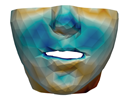

3.3. Simulation Error and Performance

- Segmentation of the maxilla and mandible. For all patients, the highest error (except for the neck, which is not clinically relevant as discussed above) appears near the cut areas, both of the maxilla (e.g., patients M5 and M7) and the mandible (e.g., patients M1 and M3). This is probably due to the presence of fixation plates and/or bone grafts in the real result (e.g., patient M10, whose maxilla was not segmented, but where the presence of bone graft has been confirmed by the surgeon who carried out the intervention). As a consequence, patients with a segmented maxilla and/or mandible show in general larger error than those without segmented bones. However, the smooth coupling method proposed in Section 2.3.3 reduces considerably the error in cut areas, as shown in Figure 2.

4.3. Comparison of Fine and Coarse Meshes